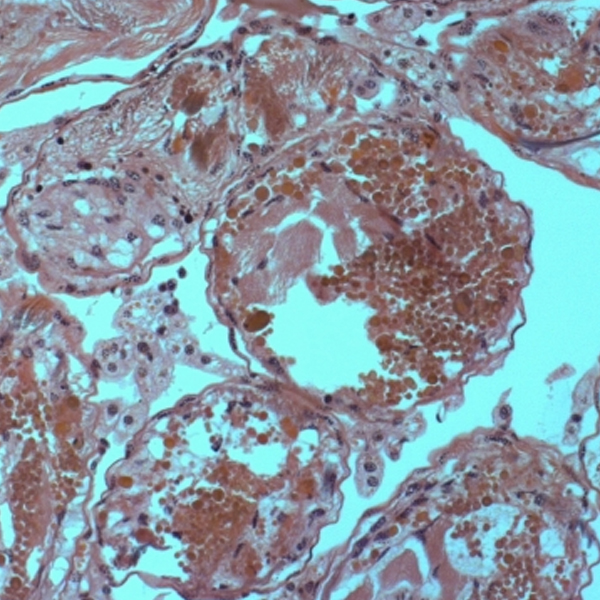

[과학쌤이오] 생명과학 동물 감수분열 슬라이드